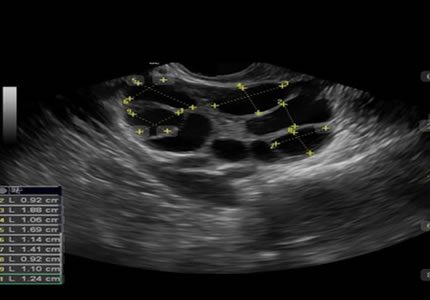

- A foundational early-cycle assessment of the uterus and ovaries. This scan evaluates your "ovarian reserve" through an antral follicle count and identifies any cysts or fibroids that may influence your upcoming cycle. It is an essential step to establish a clinical baseline before starting stimulation or treatment.

- Ideal for: Pre-treatment IVF assessment, cycle baseline evaluation, and PCOS screening.